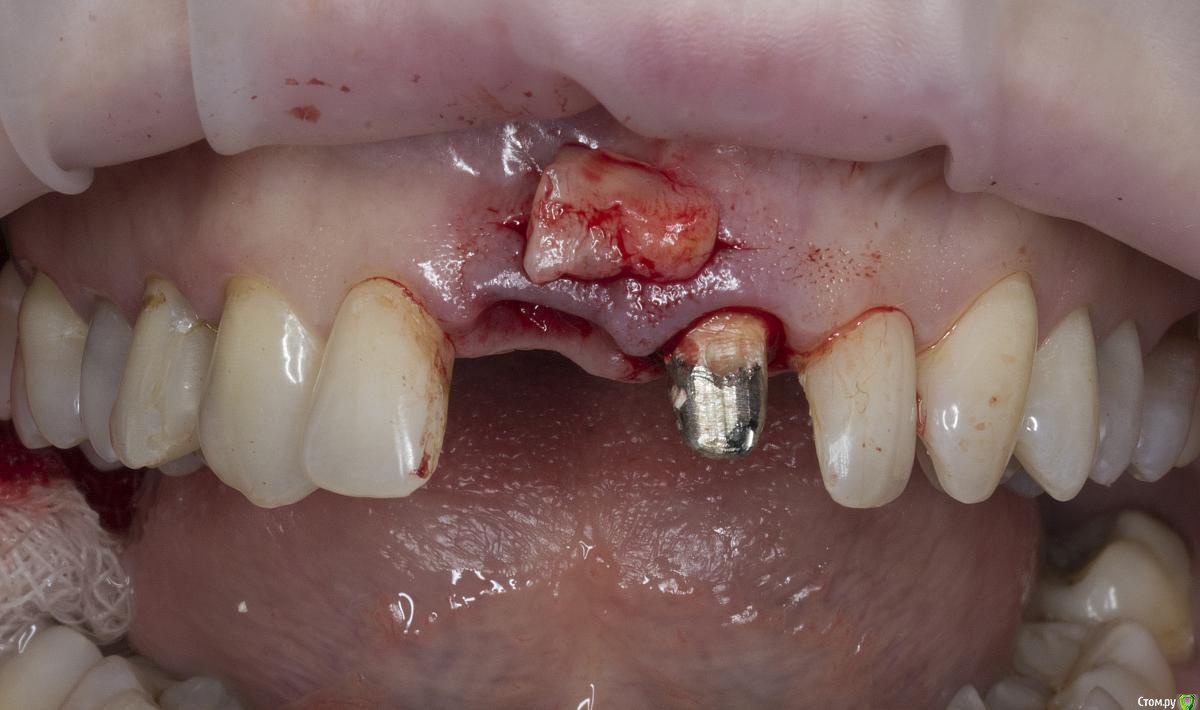

Александр07 Опубликовано 26 июня, 2020 Автор Поделиться Опубликовано 26 июня, 2020 Коллеги, скидываю фото проделанной работы, прошло около 1.5 мес, есть результат, спасибо за помощь, если какие то замечания /советы есть пишите 4 Ссылка на комментарий

колесников Опубликовано 26 июня, 2020 Поделиться Опубликовано 26 июня, 2020 (изменено) Здравствуйте! Не видел этого поста раньше,бегло посмотрел. Определенно проблема была в выборе высоты абатмент и объёме реставрации. Вы убрали композит максимально в основании-это хорошо,но абатмент оставили прежний. Следовало взять новый с высотой уступа 4-5 мм. Край коронки пришеечный следует опустить ниже,иначе десна опять отскочит. И переход слелайте на плавный а под углом,так называемый балкон. Потом будет что отдавить. По Масана сосочек сделали это хорошо и правильно,но с такой реставрацией опасно,мало место лоскуту. К счастью кажется все живы. На данном этапе рекомендую пропилить балкон и этим ограничится. Изменено 26 июня, 2020 пользователем колесников Ссылка на комментарий

Александр07 Опубликовано 27 июня, 2020 Автор Поделиться Опубликовано 27 июня, 2020 Справились одним трансплантом в итоге?)Два, один под сосочек с бугра второй вестибулярно с неба Сст 1 Ссылка на комментарий

Александр07 Опубликовано 27 июня, 2020 Автор Поделиться Опубликовано 27 июня, 2020 Здравствуйте! Не видел этого поста раньше,бегло посмотрел. Определенно проблема была в выборе высоты абатмент и объёме реставрации. Вы убрали композит максимально в основании-это хорошо,но абатмент оставили прежний. Следовало взять новый с высотой уступа 4-5 мм. Край коронки пришеечный следует опустить ниже,иначе десна опять отскочит. И переход слелайте на плавный а под углом,так называемый балкон. Потом будет что отдавить. По Масана сосочек сделали это хорошо и правильно,но с такой реставрацией опасно,мало место лоскуту. К счастью кажется все живы. На данном этапе рекомендую пропилить балкон и этим ограничится.С высотой да, выше надо было , на постоянной учтём , по балкону принцип понятен, - больше места для транса, но все же времянки рекомендуют плавными делать, без резких переходов, поэтому такой вопрос если выпиливать максимально места для тр-та то когда переводить временную коронку на плавный дизайн , через месяц где-то когда транс приживется и стабилизируется первично ? Ссылка на комментарий

колесников Опубликовано 27 июня, 2020 Поделиться Опубликовано 27 июня, 2020 Через 2 недели. Но можно и месяц Ссылка на комментарий